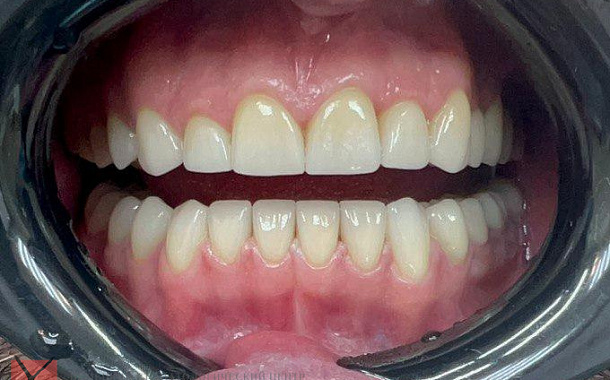

Высочайшая точность для идеальной посадки

Aoralscan 3 обеспечивает сканирование с точностью до 6,9 мкм, что позволяет создавать максимально точные цифровые слепки. Это критически важно для изготовления коронок, мостов, виниров и других ортопедических конструкций, гарантируя их идеальную посадку и долговечность.Скорость и комфорт для пациентов

- Максимально точные и эстетичные ортопедические конструкции

- Долговечные результаты